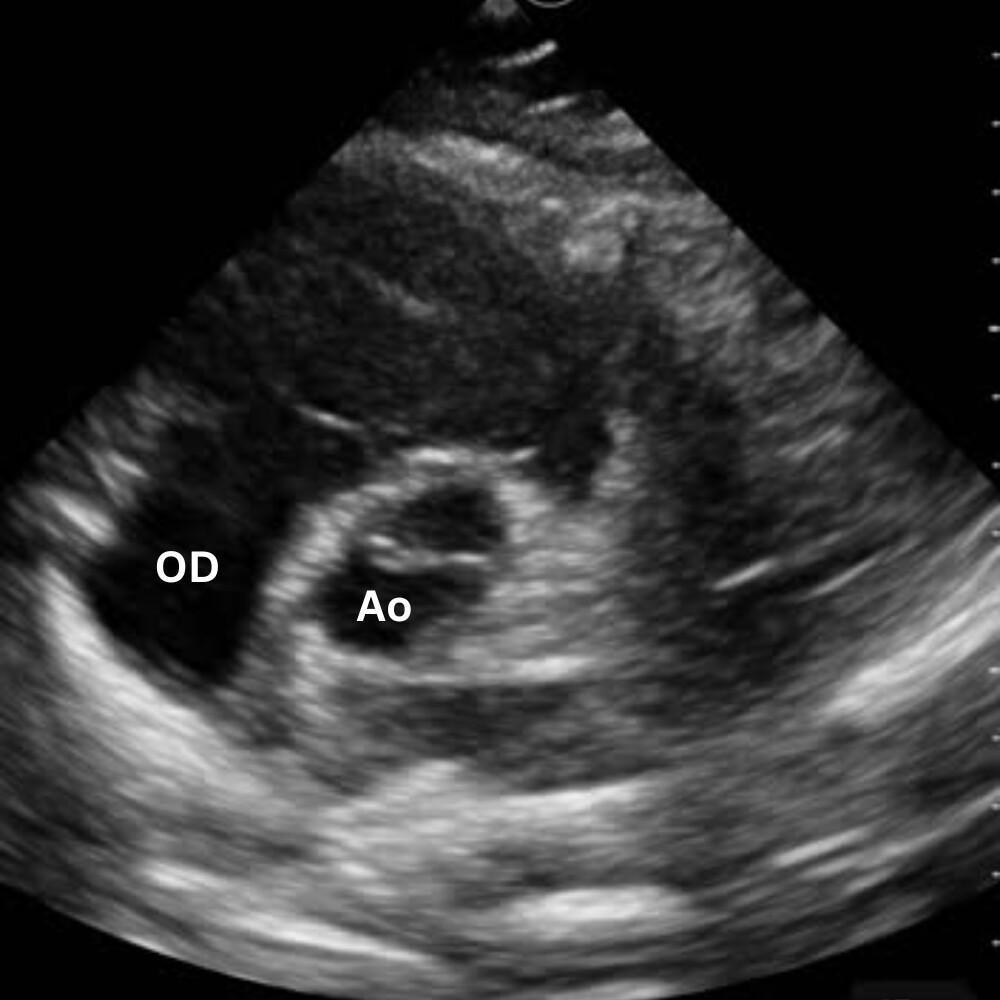

🔹 Vue Apicale Quatre Cavités

→ Quelle cavité domine ?

Placer la sonde près de l’apex (5e espace, région du mamelon gauche), marqueur vers l’épaule gauche. Glisse légèrement jusqu’à un bon espace intercostal, puis bascule la sonde vers la base du cœur jusqu’à voir VG, VD, OG et OD dans le même plan.

On visualise les quatre cavités, les valves mitrale et tricuspide et le septum.

Permet de comparer VD et VG (surcharge droite si VD ≥ VG), d’apprécier la cinétique globale et de repérer un épanchement péricardique circonférentiel.